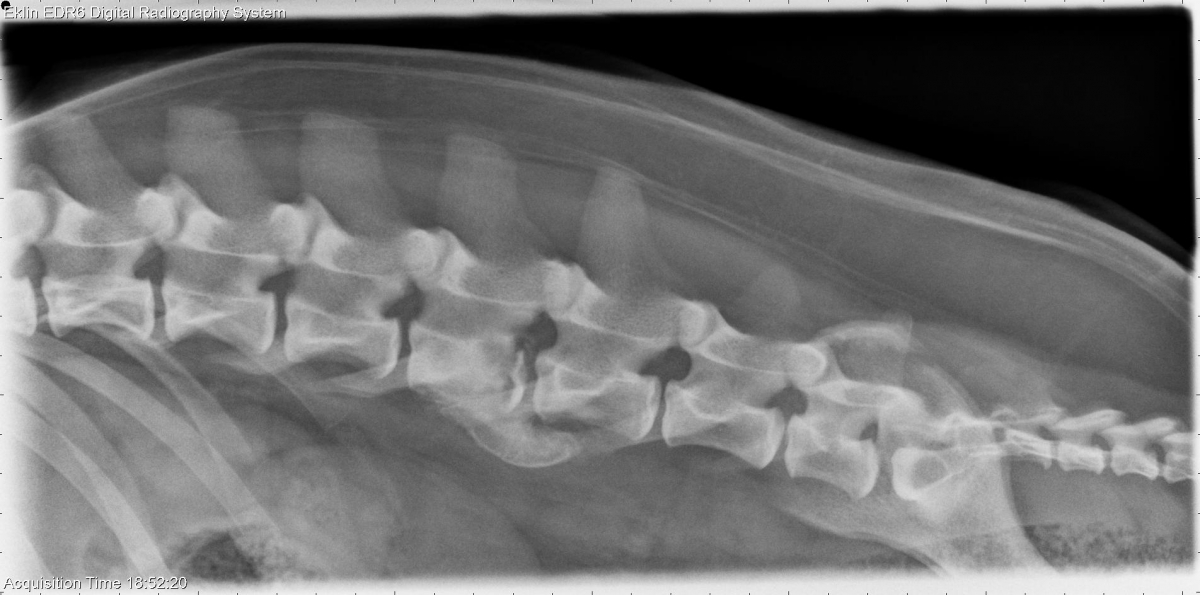

Today’s case is a 2-year-old female neutered Pit bull terrier. Fell off bed 10 days previously, acute paraparesis. What are your findings?

There is a fracture of the caudal end plate of the L4 vetebral body with adjacent sclerosis and lysis. There is ventral spondylosis deformans at this site. Mineral opacity material is present in the intervertebral foramen. The remainder of the vertebral bodies appear normal. On flexed and extended views, there is no evidence of instability.

Fracture and osteomyelitis. It is unclear which pathology is primary, and a migrating foreign body could also be involved.